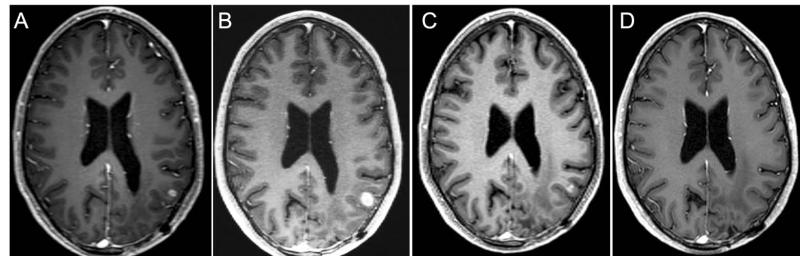

Magnetic resonance contrast-enhanced axial T1 images taken throughout the course of treatment for a 36-year-old man with IDH wild-type MGMT promoter methylated GBM

Magnetic resonance contrast-enhanced axial T1 images taken throughout the course of treatment for a 36-year-old man with IDH wild-type MGMT promoter methylated GBM are shown 7 weeks before selinexor (A), at baseline 1 week before selinexor (B), and during a partial response after 16 weeks of treatment (C), and then complete (D). Response beginning after 24 weeks of treatment and confirmed after 32 weeks of treatment (not shown).